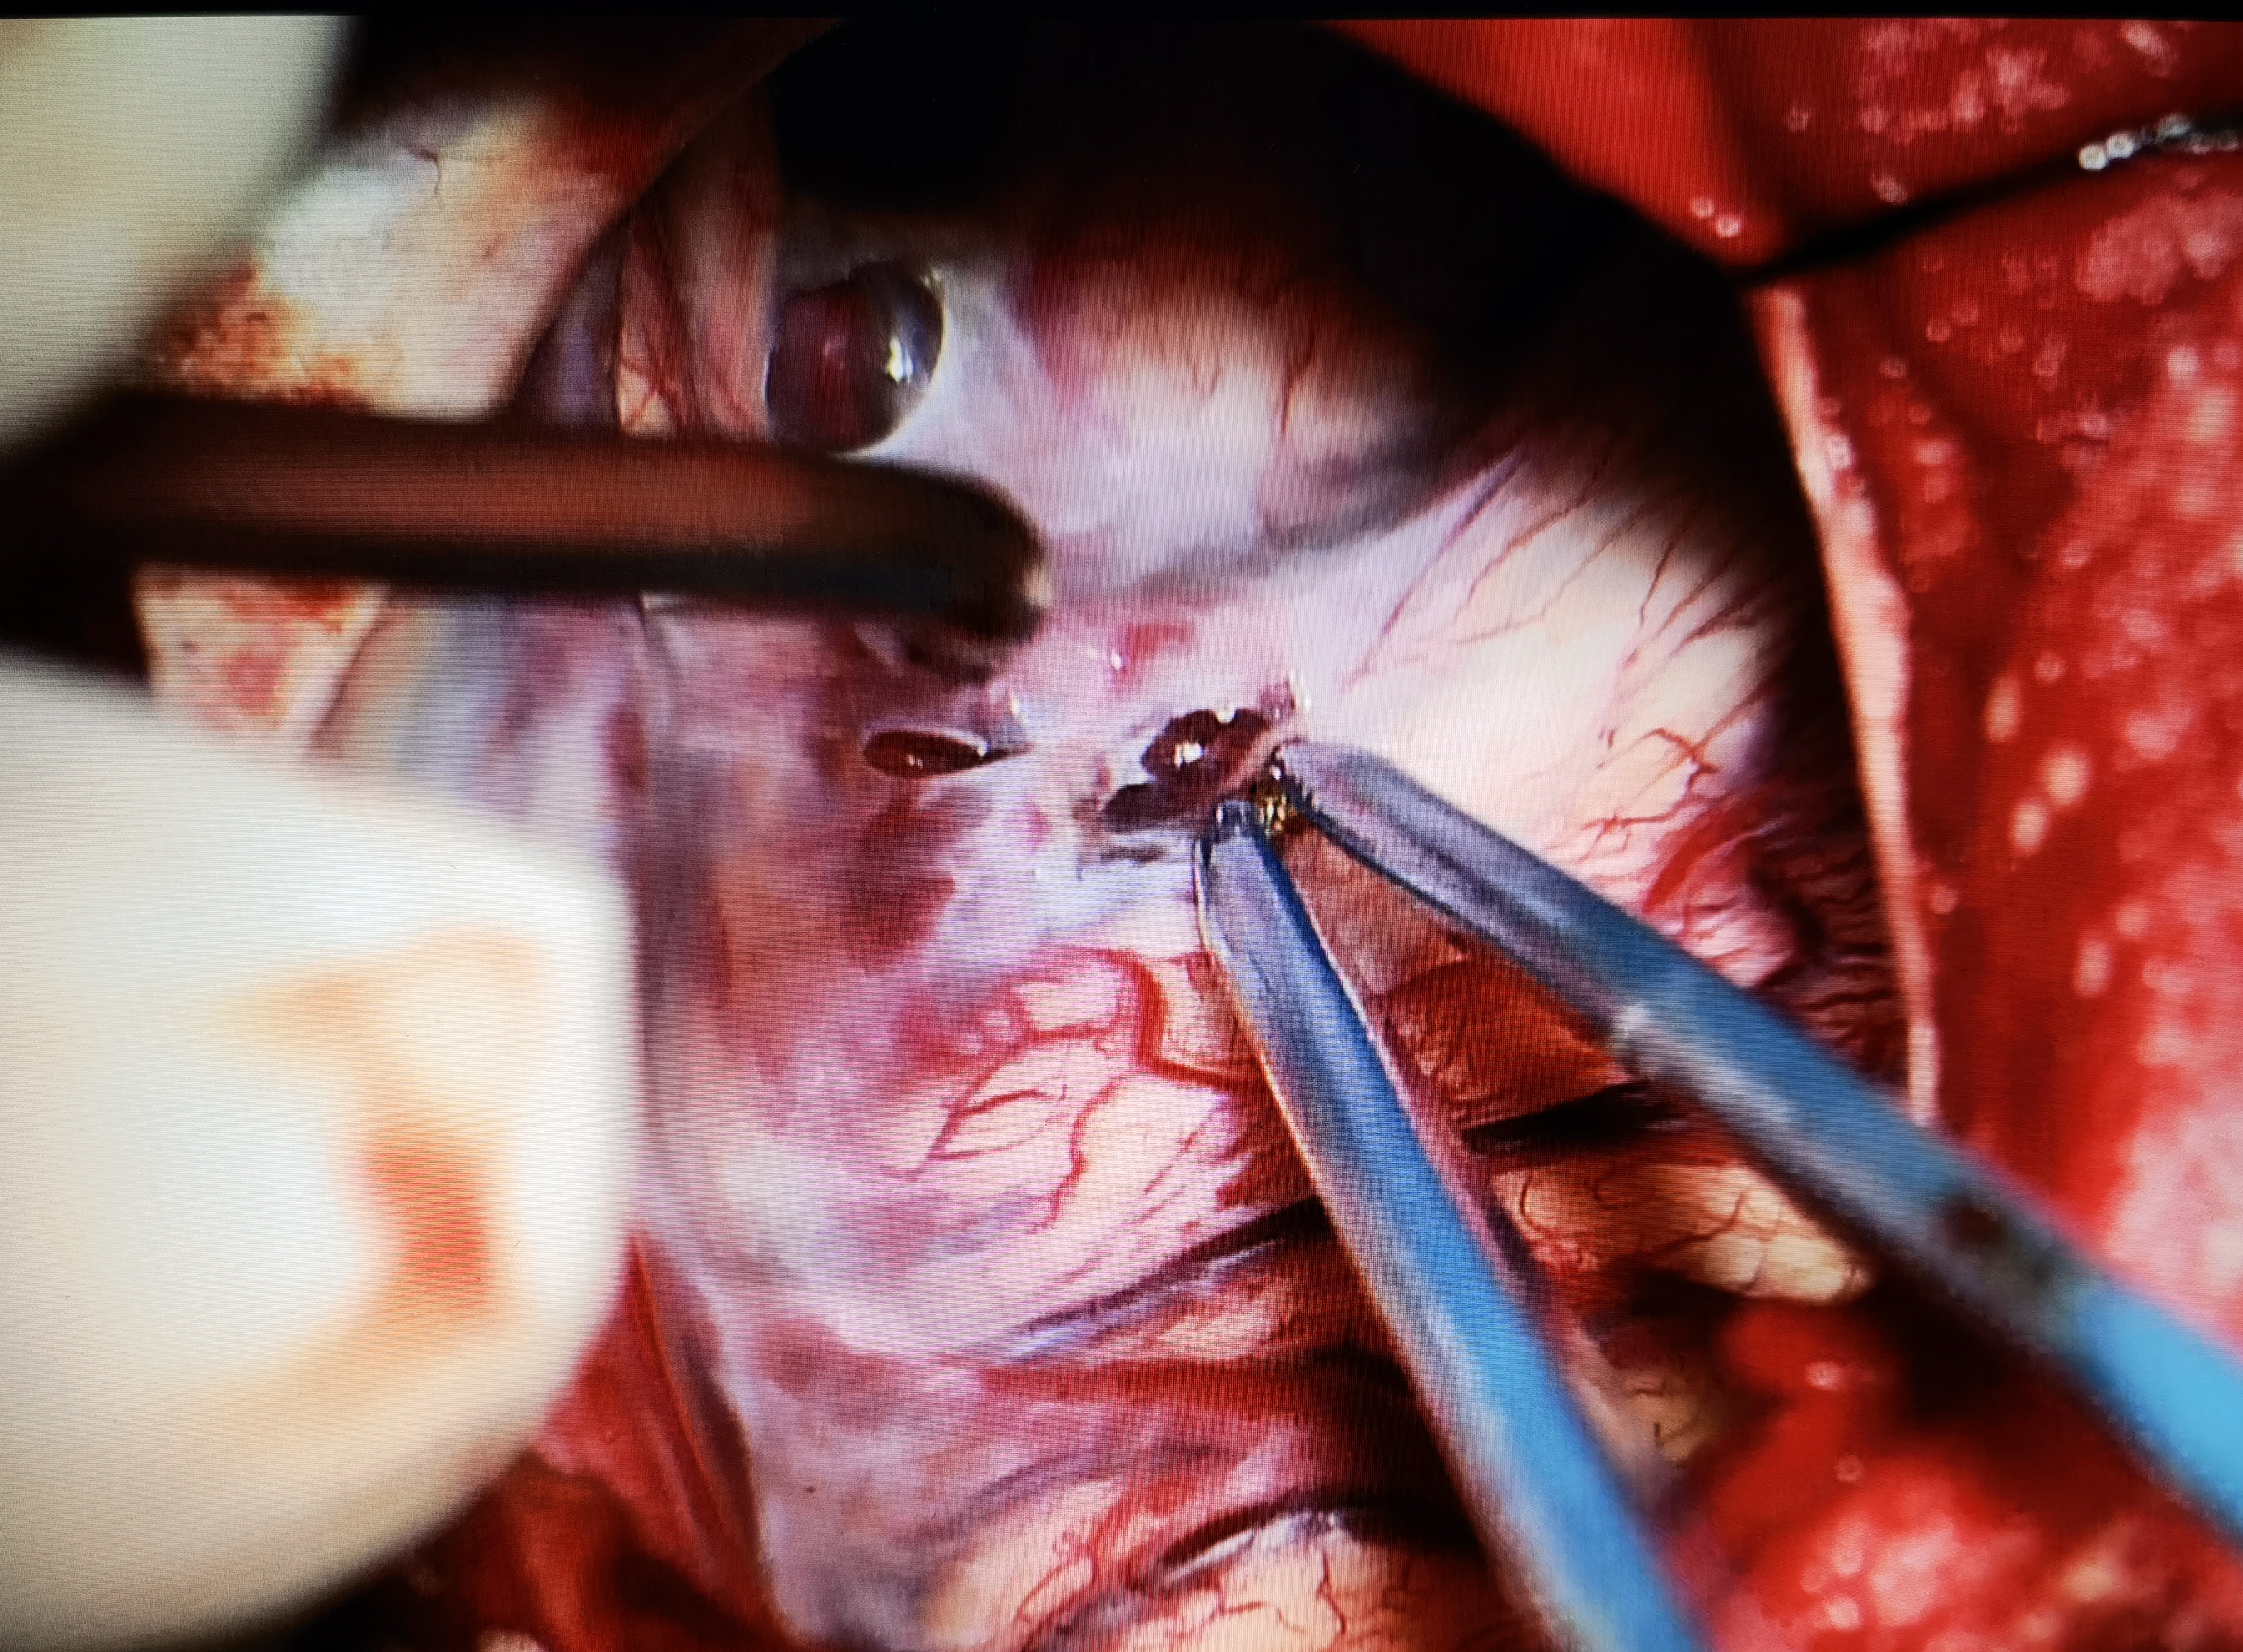

考虑到患儿囊肿体积巨大,占位效应明显,向患儿家属交代病情及手术风险后,行小骨窗开颅蛛网膜囊肿-脑池造瘘术,术中打通侧裂池、颈动脉池、基底池,多处造瘘,瘘口大小为1-1.5cm,并切除部分囊壁。术后患儿无新发症状,病情恢复良好,定期复查随访。

术中造瘘